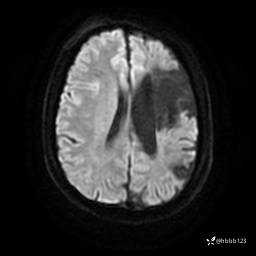

患者男,43岁。

简要病史:癫痫患者复诊,昨日发作5-6次,建议住院进一步治疗。

入院完善脑癫痫组合序列:

DWI: